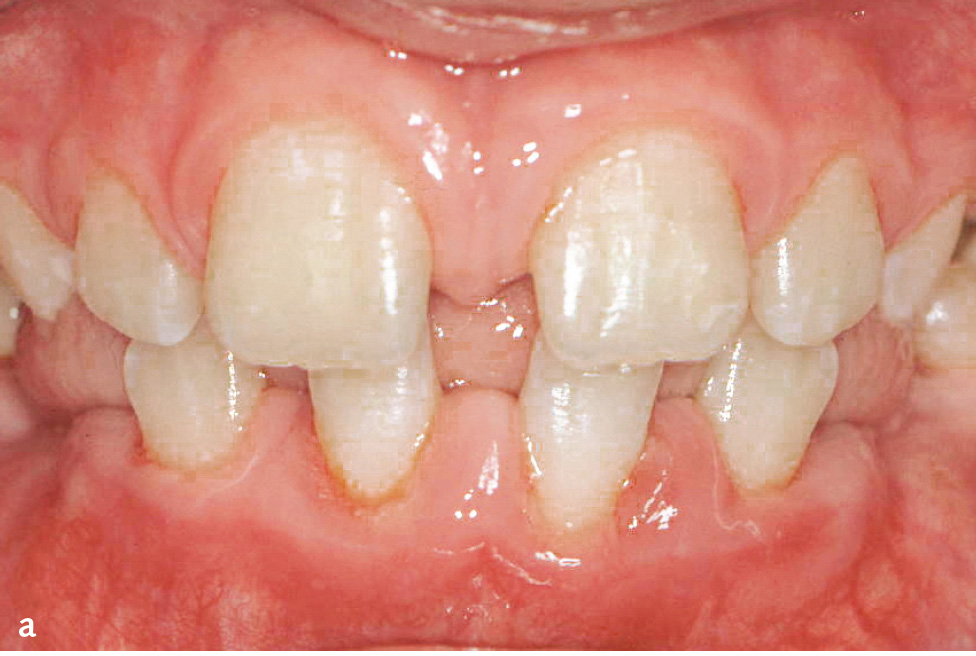

Das Papillon-Lefèvre-Syndrom (PLS; Keratosis palmoplantaris – Periodontopathie; ORPHA678/ICD-10: Q82.8) beschreibt seltene, autosomal-rezessiv erbliche Mutationen des Kathepsin-C-Gens, die zur Inaktivität dieser Cysteinprotease führen. Kathepsin C aktiviert die Serinproteasen (Elastase, Kathepsin G, Protease 3, Neutrophilen-Serinprotease 4) der neutrophilen Granulozyten. Damit ist die erste Linie der parodontalen Infektabwehr beeinträchtigt. Die charakteristischen Symptome sind palmoplantare Hyperkeratosen mit einer bereits im Milchgebiss einsetzenden und sehr rasch verlaufenden Parodontitis (Abb. 1a bis d). Allerdings sind auch atypische Verläufe bekannt, bei denen entweder nur Hautsymptome oder nur die im Milchgebiss einsetzende und rasch verlaufende Parodontitis auftreten6. Die Häufigkeit beträgt 1–4:1.000.000. Untersuchungen der neutrophilen Granulozyten haben in manchen Fällen gestörte Zellfunktionen wie eine verminderte Motilität, Chemotaxis und Phagozytose sowie eine verminderte Produktion von Sauerstoffradikalen gezeigt, die sich in manchen Fällen nach der therapeutischen Intervention normalisierten. In der subgingivalen Plaque werden zumeist vermehrt anaerobe gramnegative Keime und vor allem Aggregatibacter actinomycetemcomitans nachgewiesen.

Abb. 1a bis d Männlicher Patient mit Papillon-Lefèvre-Syndrom: a) klinische Ansicht im Alter von 7 Jahren und 9 Monaten (vor Therapie: ausgeprägte Mobilität der Unterkieferschneidezähne, Sondierungstiefen an ersten Molaren und Unterkieferschneidezähnen von 9 bis 15 mm); b) Panoramaschichtaufnahme; Hyperkeratosen an c) Hand- und d) Fußflächen (Abbildungen aus Kugel et al. 20015).